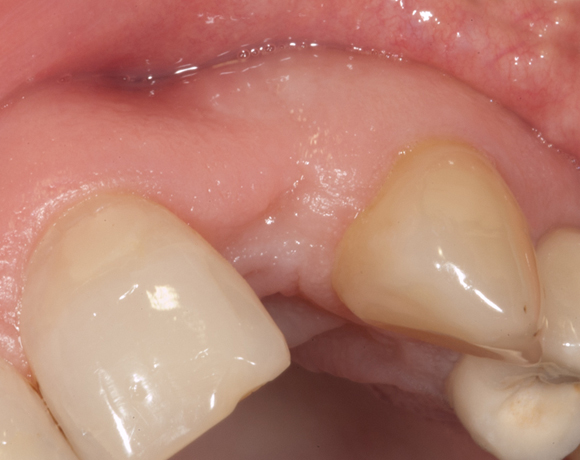

Im vorliegenden Patientenfall musste der Zahn 22 nach erfolgloser Endodontie entfernt werden. Die Nachbarzähne waren kariesfrei, es wurde eine Marylandbrücke (eine Brücke mit zwei Flügelchen, die palatinal an den Nachbarzähnen verklebt werden) oder ein Implantat besprochen. Die Patientin hat sich für ein Vollkeramikimplantat entschieden. In der Diashow wird der operative Eingriff bis zur fertigen Krone gezeigt. Die Einheilzeit betrug drei Monate.